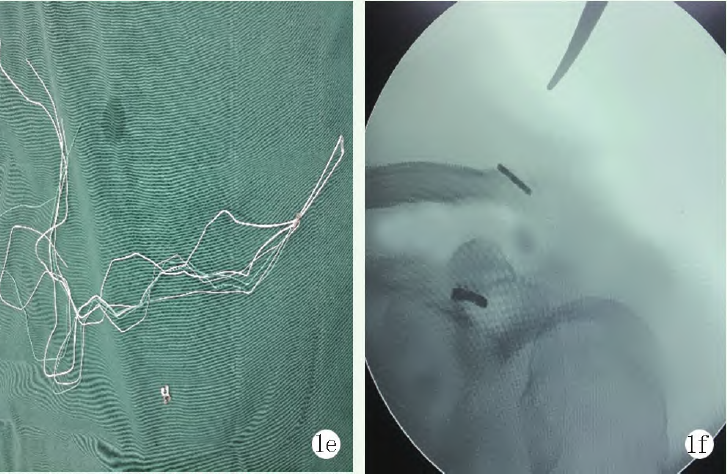

將可調節(jié)袢鈦板遠端留出足夠長度后(圖1e),牽引線將可調節(jié)袢鈦板引出鎖骨側。然后將四葉草型袢鈦板套在可調節(jié)袢的遠端,此時按壓復位后慢慢收緊可調節(jié)袢的收緊線,C形臂X線機透視復位滿意后打結固定(圖1f)。

1e: 可調節(jié)帶袢鈦板及四葉草鈦板

1f: 固定后術中透視見肩鎖復位及鈦板位置滿意